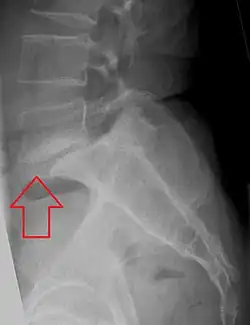

Retrolisthesis

Grade 1 retrolistheses of C3 on C4 and C4 on C5

A retrolisthesis is a posterior displacement of one vertebral body with respect to the subjacent vertebra to a degree less than a luxation (dislocation). Retrolistheses are most easily diagnosed on lateral x-ray views of the spine. Views, where care has been taken to expose for a true lateral view without any rotation, offer the best diagnostic quality.

Retrolistheses are found most prominently in the cervical and lumbar region, but can also be seen in the thoracic area.